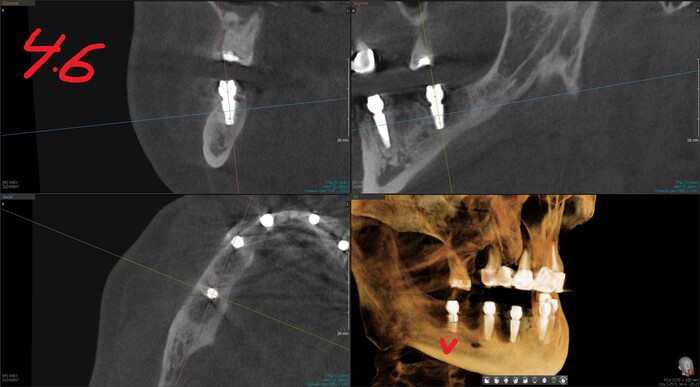

КЛКТ

Да и смысл добавлять скан - всё видно и понятно. На нижней челюсти 4 зуба, которые никуда не годятся.

Справа - одинокий воин.

Слева - компания друзей навынос.

Белые точки на нижней челюсти - маячки.

Позиция 4.6

Имплантолог видит, сколько мм можно докрутить безопасно для структур челюсти (нервов, сосудов). Делает дело.

Сделали КЛКТ:

Что бы точно никаких вопросов не осталось у доктора, сделали ОПТГ:

ОПТГ